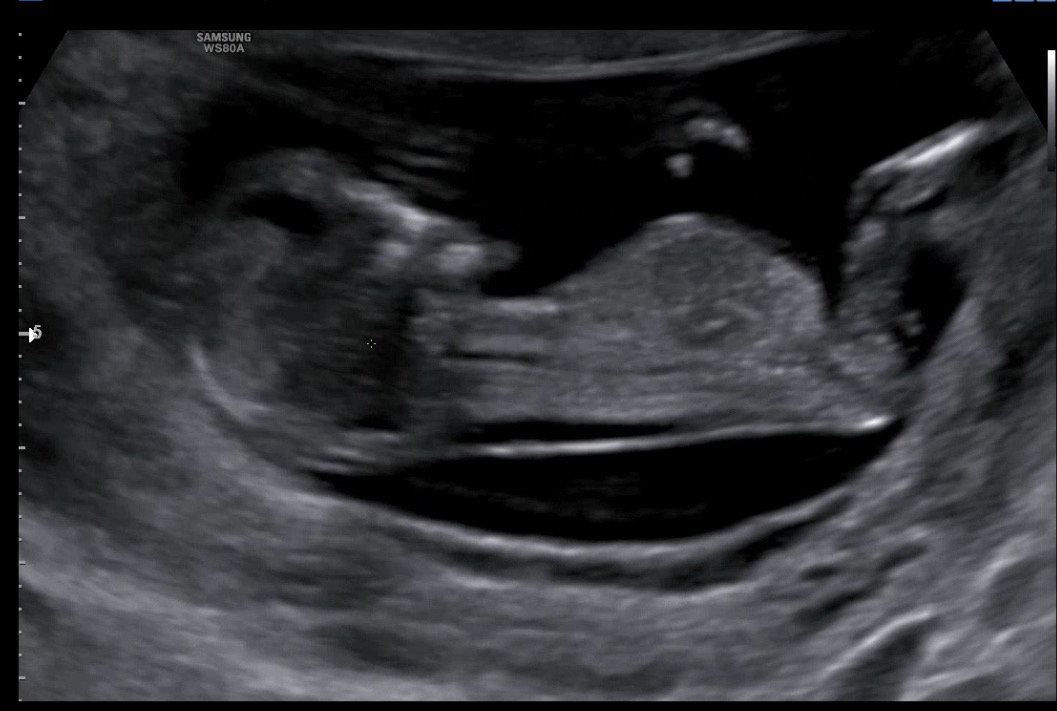

12주2일 성별 투표해주세요~~

12주2일 초음파 보고 왔어요~ 각도법 잘 보시는분들 투표 부탁드립니다!